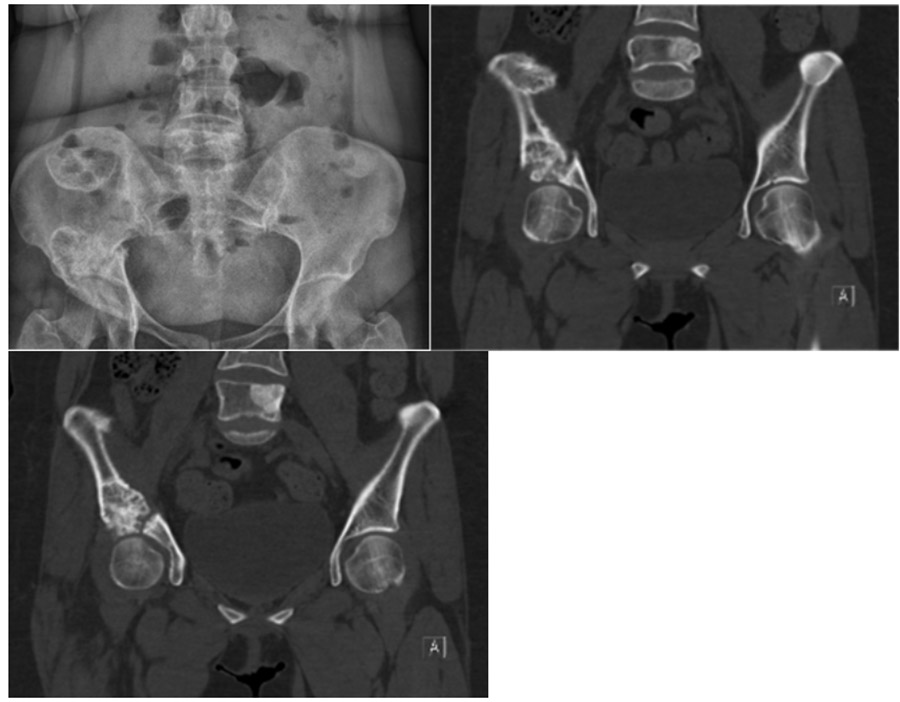

CASE 19: Fracture development due to breast cancer metastasis to the hip bone (acetabulum).

Before the surgery: X-ray and CT scans show metastases in multiple foci and a pathological fracture of the right acetabulum.